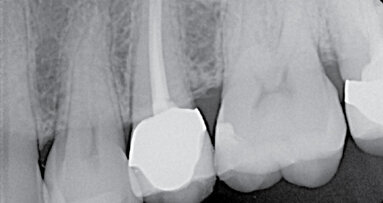

Prvním možným řešením je umístění MTA přímo do dekontaminovaného apexu zubu. U kratších rovných kořenů jde se správným instrumentáriem o poměrně snadný výkon. V případě 12letého chlapce referovaného po fraktuře zubu šlo ale o postranní řezák 12 s výrazným apikálním zahnutím, kam bylo s rigidní zahnutou koncovkou tzv. „MTA gun“ v roce 2011 nemožné aplikovat dostatečně hluboko. V dnešní době s flexibilními koncovkami MAP systému by zřejmě tento problém neexistoval. Přestože nebyl zub zcela zaplněn, předchozí dekontaminace a potentní dětská tkáň zajistily, že se veškerý zbývající prostor kořene vyplnil zřejmě dentinoidní tkání. Zub byl opatřen adhezivní dostavbou s FRC čepem a pryskyřičnou korunkou. (Obr. 1–3)

Popsané řešení má výbornou prognózu.